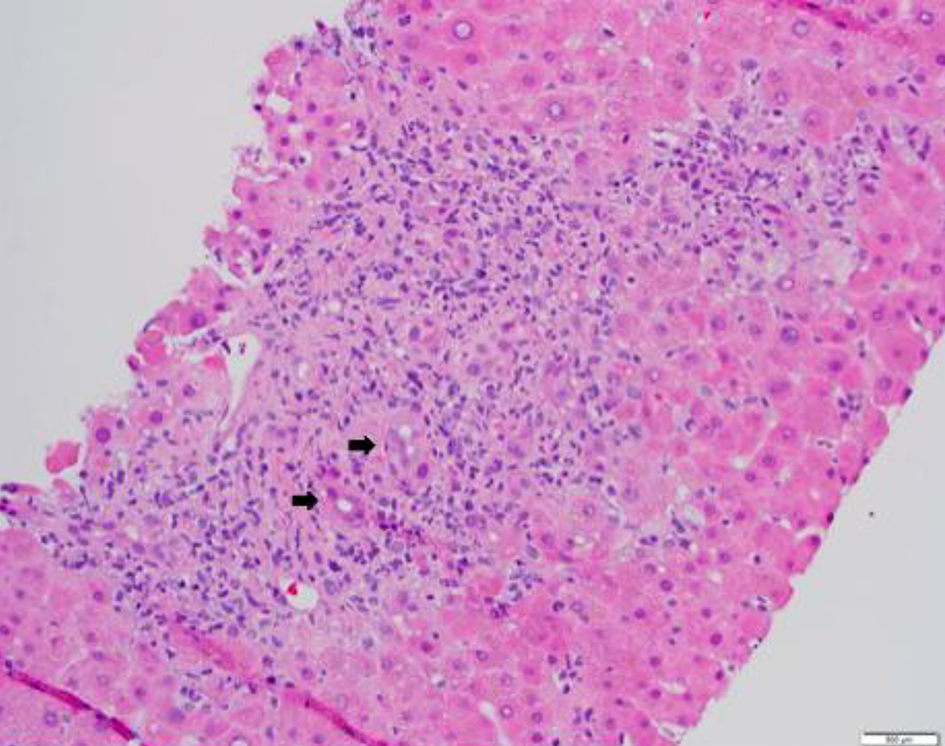

![]() Click for large image | Figure 2. Liver tissue with features of graft-versus-host disease. Histologic section of a core liver biopsy shows mixed portal inflammatory infiltrates composed of neutrophils, lymphocytes and occasional plasma cells. There is extensive bile duct injury and interface hepatitis. Black arrows indicate damaged bile ducts (hematoxylin-eosin, original magnification, × 200). |